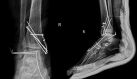

Case summary: We report a very rare injury of closed TTD with a follow-up period of 36 mo. Initial closed reduction was not successful because of a fractured highly unstable medial malleolus displaced into the ankle mortise, blocking the relocation of the talus. The patient was able to walk pain-free after the 3rd month of surgery. At the 36-mo follow-up, there were 10 degrees of flexion loss and 10 degrees of extension loss in the tibiotalar joint. Furthermore, 5 degrees of subtalar joint inversion-eversion loss was present.